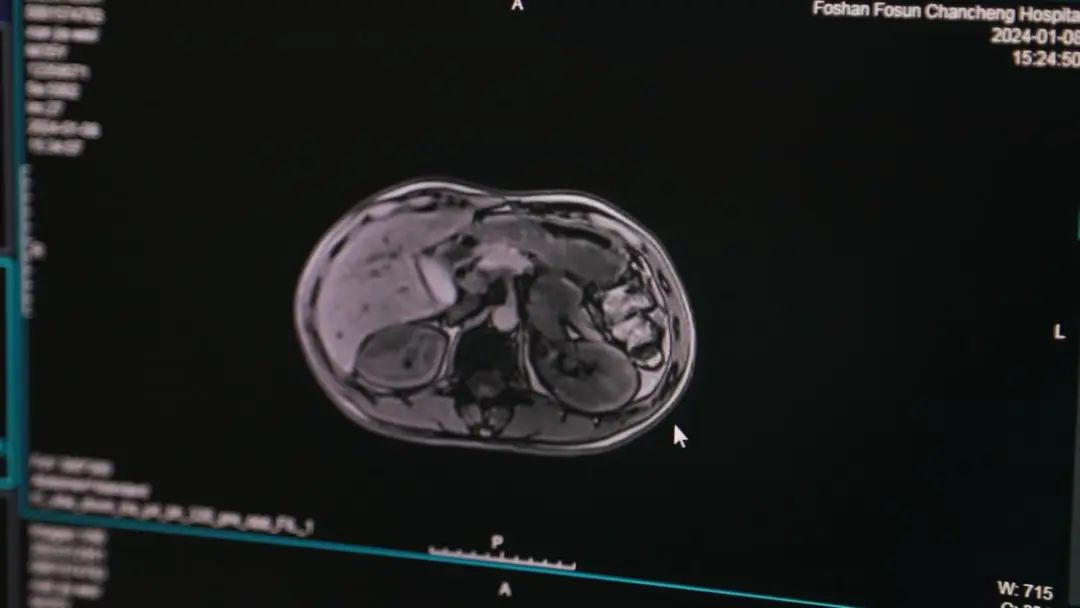

冼先生来自肇庆四会,今年32岁,左腹部反复隐痛一年,一直不以为意。“我起初以为是胃不舒服,直到后来,疼痛的持续时间开始加长,到医院检查才发现,是左侧的腹膜后长了一个约10厘米大的肿瘤。”冼先生回忆道。

经过详细检查,医生明确这个肿瘤是长在肾上腺外的嗜铬细胞瘤(副神经节瘤),可分泌儿茶酚胺。这种物质可以使病人血管收缩,常合并高血压,有时患者的血压会骤升至180mmHg以上。据统计,每1000名高血压患者里,就有1-5人是因为这种嗜铬细胞瘤(副神经节瘤)导致的。

更棘手的是,冼先生的这颗肿瘤位于左侧腹膜后,极紧贴胰腺,底部更是与腹主动脉和肾动静脉黏连密切。若想要进行切除,手术中很有可能会损伤到上述的重要器官和血管。